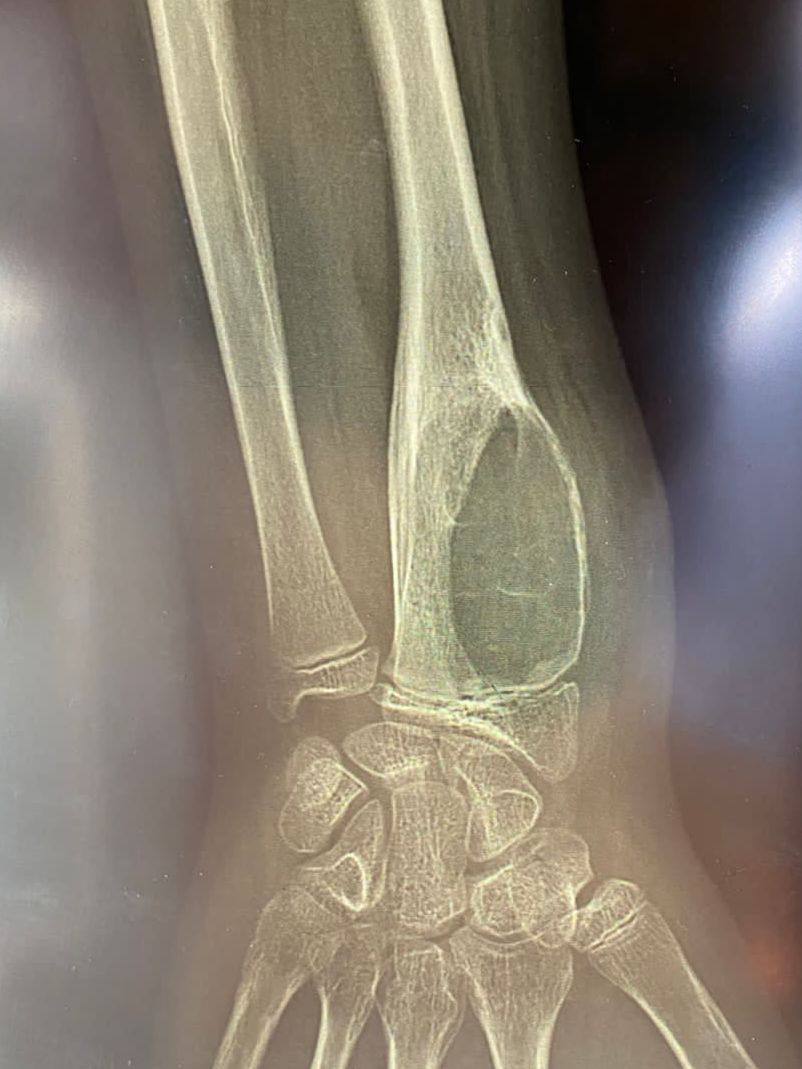

В больницу доставили 12-летнего ребенка с диагнозом «аневризмальная киста лучевой кости».

— Это доброкачественное опухолеподобное поражение костей, состоящее из многочисленных сосудистых пространств, заполненных кровью, — объяснили в ОДКБ.

В ноябре 2022 года ребенку проводили экскохлеацию образования и гистологическое исследование. После этого провели костную пластику аллотранспантатом. Тогда подтвердился диагноз «аневризмальная киста».

Врачи провели промывание полости кисты аминокапроновой кислотой. Но через полгода патология осталась без изменения.

— В сентябре была проведена повторная операция — резекция патологически измененных тканей, а также костная пластика аутотрансплантатом — это собственная костная ткань человека, — рассказали в больнице.